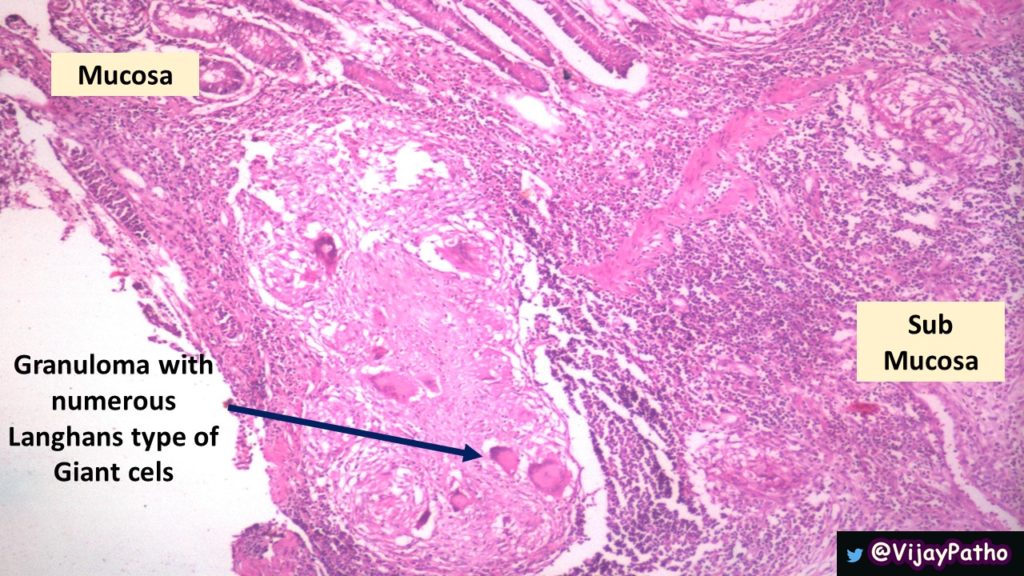

Микроскопический взгляд на мишитарный туберкулез легкого: фотодокументация